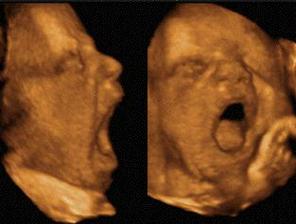

zázrak lidské života na videu